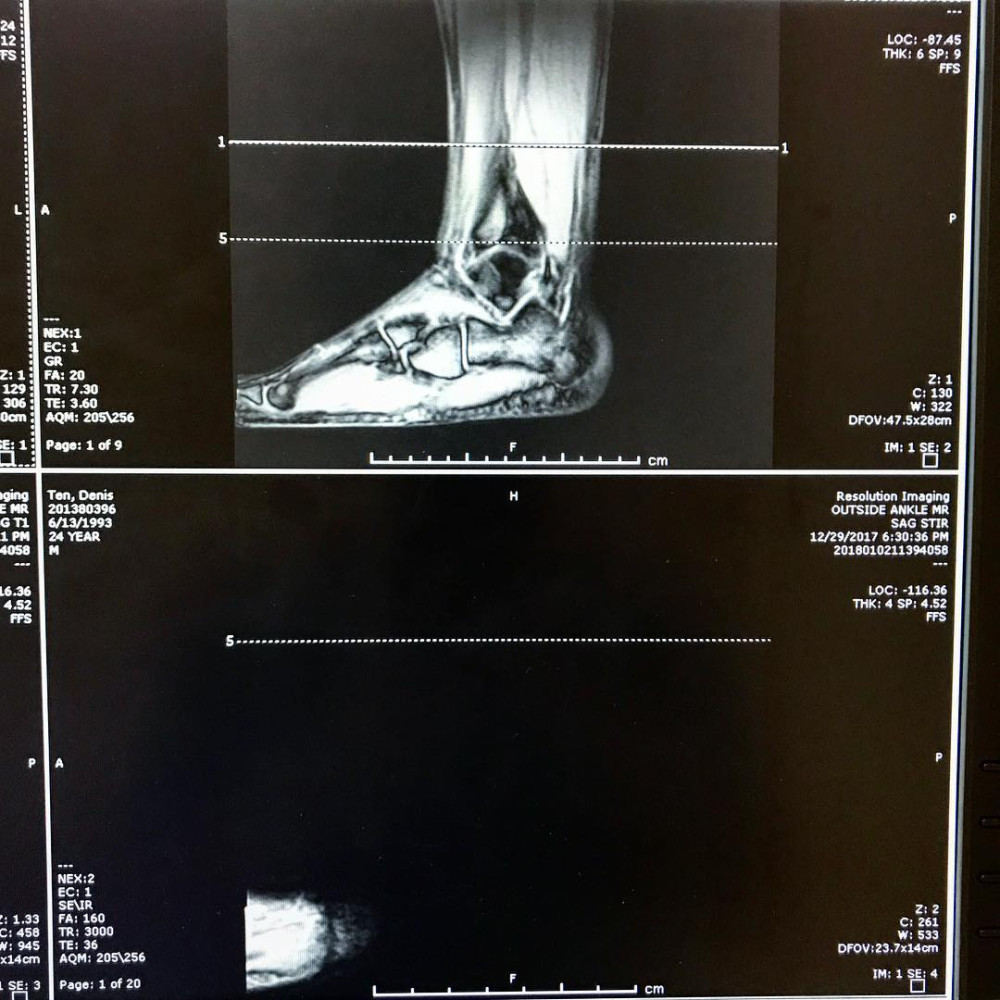

Олимпийский призер Денис Тен опубликовал на воей странице в Instagram МРТ-снимок своей травмированной ноги,  передает корреспондент BNews.kz.

Тен пояснил, что МРТ сканирование отобразило, как связки стали соединяться между с собой. Также уменьшился костный кровоподтек.

«Если первое дестабилизировало ногу, то второе вызывало резкие боли. Для полного восстановления потребуется еще около 6 месяцев, но думаю к Олимпиаде, я как раз приду в оптимальной кондиции», - добавил он.